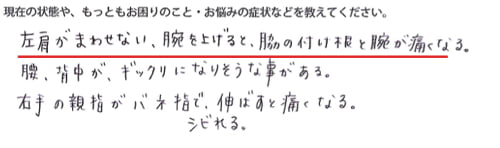

左腕がまわせない。腕を上げると脇の付け根と腕が痛くなる。

とにかく改善したいのはお仕事に支障が出てしまうので

左肩・左腕が上がる、物を上まで持ち上げれるようにしたい。

とのご希望でした。

そして右手の親指はこの辺りに痛みがあるそうです。

さらに腰のこの辺りにも痛みが・・。

これらの症状は3ヶ月くらい前から・・・

原因はやはりお仕事の頑張りすぎのようでした。